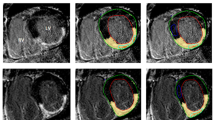

LA LGE scans were analysed using ADAS ® image post-processing software (Galgo Medical SL, Barcelona, Spain). On all axial images the atrial blood pool was initially segmented and atrial wall was interpolated automatically into a 3D shell, which was manually adjusted. To avoid epi- or endocardial artefacts or partial volume effects, the software was set to create a single mid-myocardial layer, which was manually adjusted according to MRI images to represent mid-atrial wall. Inflow artefacts were excluded. Pulmonary veins and mitral valves were excluded for fibrosis analyses. Pixel intensities were calculated automatically and shown on the 3D shell. Atrial wall pixel intensities and mean blood pool intensity were exported from ADAS ®. Image intensity ratio (IIR) values of all atrial wall pixels were calculated as atrial wall pixel intensity divided by mean blood pool intensity) (see Fig. 1).

Example of left atrial late gadolinium enhancement image. A original image. Blood intensity is 60 and image intensity ratio threshold hence (60 × 1.2 =) 72. B depicts segmented atrial wall, blue indicating atrial wall below threshold, red indicating atrial wall above threshold. RA right atrium, LA left atrium, Eso esophagus, LV left ventricle, Ao aorta